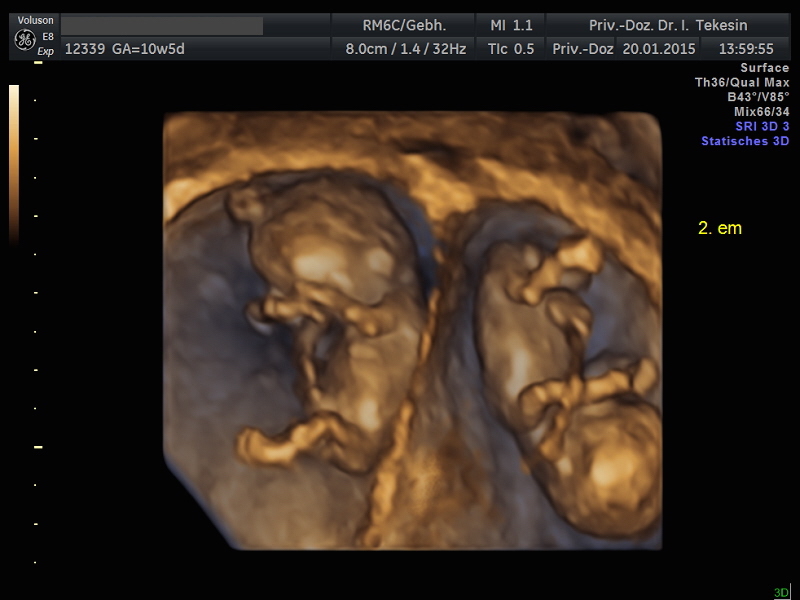

Kind in der 12. Woche (3D-Darstellung)

Kind in der 13. Woche (3D-Darstellung)